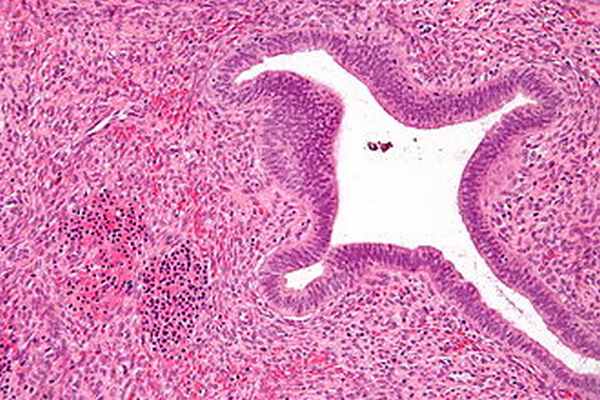

Микрофотография показывая ядросодержащие эритроциты (внизу слева изображения), один из элементов, необходимых для вызова экстрамедуллярного кроветворения, в полип эндометрия. H&E пятно.